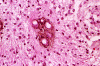

A 5 year-old Boy with Nausea and Vomiting for Three Months.

These photos were obtained from the formalin fixed paraffin embedded sections.

Jones stain